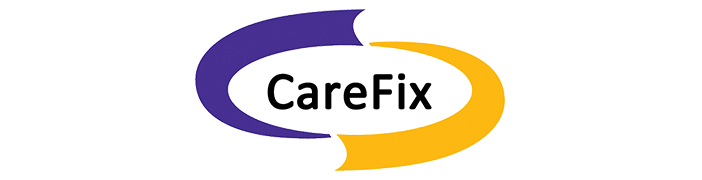

Locking Plates: What Have We Learned? Although traditional plate designs date back decades, these authors discuss the emergence and potential of locking compression plates, polyaxial locking plates, and minimally invasive plate osteosynthesis. HYPERLINK "https://s3.amazonaws.com/HMP/hmp_ln/imported/pt0915locking1ab.png" \t "_blank" The popularization of traditional plate and screw constructs dates back to the late 19th century as well as the efforts of the Belgian surgeon Robert Danis, MD.1,2 This discovery along with Danis’ publication of Over the past several decades, as surgeons have gained a better understanding of the utility of plate and screw constructs, the application of the devices has evolved. In addition to incorporating these devices into the surgical repair of fractures, surgeons may utilize them for joint arthrodesis and other reconstructive osseous surgeries. One advance with these modalities has been the advent and evolution of the locking plate construct, which has several applications within foot and ankle surgery. Reviewing The Different Kinds Of Plate Fixation HYPERLINK "https://s3.amazonaws.com/HMP/hmp_ln/imported/pt0915locking1cd.png" \t "_blank" Neutralization plates function as load-sharing apparatuses that shield lag screws from the torsional forces the surgeon encounters during range of motion.4 Buttress plates and anti-glide plates are load-bearing devices that can support a section or segment of bone, which are frequently areas of impaction associated with significant comminution of the cortex, thus leaving a compromised diaphyseal construct and/or voids within the cancellous bone. By fixing the plate proximally and distally to stable areas of bone, the surgeon can prevent the segments from re-approximating during axial loading.5 There are two kinds of compression plates: static compression plates and dynamic compression plates. With the static compression plate, the compression yielded at the fracture interface is secondary to the tension one applies to the implant. This technique is beneficial for those transverse or short oblique fractures when insertion of a lag screw is not attainable. In order to achieve compression, drill the initial screws eccentrically through oval holes in the plate away from the fracture site. As the screw heads contact the plate and sit centrally in the oval holes, the fragments compress together. The dynamic compression plate adheres to the tension band principle. This refers to the application of a plate on the tension (convex) side, preventing gapping that normally would occur and converting the distracting forces into compression forces. The placement of a plate to bone serves as both an expediter and a temporary inhibitor of osseous repair.5 HYPERLINK "https://s3.amazonaws.com/HMP/hmp_ln/imported/pt0915locking2abc.png" \t "_blank" Certain plate designs have addressed the effects of reduced blood flow that can occur underneath a plate due to reduced bone density. This plate-associated osteoporosis has a detrimental effect on the mechanical properties of healing bone. Limited contact dynamic compression plates were designed with recesses or undercuts in the plate to reduce contact between the plate and the bone, therefore reducing the risk of plate-associated osteoporosis. Recognizing The Potential Benefits Of Locking Compression Plates There have been efforts to improve the weakest part of the construct (the screw-bone interface) by increasing the contact area between the screw and the bone with the placement of screws in polymethyl methacrylate (PMMA) or by creating a single-beam construct. This is the principle behind locking plates with the creation of a construct to address the lack of motion between the components of the beam (i.e., the plate, screw and bone).6 HYPERLINK "https://s3.amazonaws.com/HMP/hmp_ln/imported/pt0915locking2def.png" \t "_blank" The locking compression plate arose from the desire to increase stability, which at the time was limited by the torque generated during screw purchase into the plate-bone interface. Cancellous, osteoporotic or pathologic bone and comminution limit the amount of torque that one can generate to enhance stability.7 This led to the development of the locking compression plate, which has the ability to preserve the blood supply to bone by reducing periosteal stripping. The traditional plating techniques provided stability by compressing the plate to the bone surface with the screws achieving bicortical purchase as the second point of fixation. However, locking compression plate technology features unicortical locking screws that can be an “internal fixator” that can act as a bridge over compromised bone.8 However, in areas or regions where high torsional and axial loads are expected, one should utilize bicortical locking screws. With locking plates, the sum of all the interfaces between the screws and bone equals the strength of fixation as opposed to the unlocked plates’ single screw pullout strength.7 One of the benefits of locking plates is their ability to be “bridge plates,” whereby they provide excellent axial and angular stability, preserve fragmentary blood supply, and reduce the risk of loss of reduction. Indeed, surgeons do not have to contour these plates anatomically to the bone, and the plates have the potential benefit of providing superior fixation in osteoporotic bone. Indications for the use of locking plates include diaphyseal/metaphyseal fractures in osteoporotic bone, multifragmentary diaphyseal/metaphyseal fractures, osteotomies in at-risk patients (poor bone stock, revisions, etc.), articular fractures, segmental fractures with multiple patterns, and any combination of the above.9 HYPERLINK "https://s3.amazonaws.com/HMP/hmp_ln/imported/pt0915locking3ab.png" \t "_blank" In their guidelines for using the locking compression plate, Gautier and Sommer emphasize the importance of the reduction technique, minimally invasive plate insertion and fixation to keep bone viability undisturbed.9 Pertinent Insights On Minimally Invasive Plate Osteosynthesis HYPERLINK "https://s3.amazonaws.com/HMP/hmp_ln/imported/pt0915locking3cd.png" \t "_blank" Minimally invasive plate osteosynthesis maintains bone vascularization with minimal periosteal stripping, thus improving bony consolidation and decreasing operative time, complications and infection rates. The application of a locking plate using the minimally invasive plate osteosynthesis technique generally consists of making small incisions proximal and/or distal to the fracture site, percutaneous reduction and subsequent extraperiosteal placement of the plate with any radiolucent percutaneous guide. Can Polyaxial Locking Plates Have An Impact? A recent study by Cullen and colleagues looked at a biomechanical comparison of polyaxial and uniaxial locking plate fixation in extra-articular proximal tibia metaphyseal fractures.10 A Closer Look At Potential Contraindications And Complications Currently, there are no absolute contraindications for locking plates. However, there are instances when applying them may be unnecessary. A good example would be in a case with a simple fracture pattern in a healthy patient with good quality bone. Another case would be a fracture pattern where the surgeon is trying to achieve compression through the plate itself without the addition of a lag screw. Also, if a patient has an oligotrophic non-union and the cause of the delayed healing is not related to an insufficient amount of stability, one should not employ locking plates. Another matter to keep in mind is the increased cost of a locking plate-screw construct versus traditional plate-screw designs, which in some cases can be substantial. As always, consider the possibility of a metal allergy or intolerance. HYPERLINK "https://s3.amazonaws.com/HMP/hmp_ln/imported/pt0915locking4def.png" \t "_blank" One of the more common complications with locking plates is creating an environment of too much stability, thus becoming “non-union generators.”11 Final Thoughts As we previously discussed, it is important to tailor the fixation of choice to the fracture pattern and location, the underlying bone quality and the overall needs of the patient. We still need to see more clinical data on locking plate technology in order to determine specific clinical scenarios in which the additional cost may be justified. Dr. Fidler is a Fellow at the Orthopedic Foot and Ankle Center in Westerville, Ohio. Dr. Prissel is a Fellow at the Orthopedic Foot and Ankle Center in Westerville, Ohio. Dr. Hyer is the Fellowship Director of the Advanced Foot & Ankle Surgical Fellowship in Westerville, Ohio. He is a Fellow and a member of the Board of Directors for the American College of Foot and Ankle Surgeons. References 1 2 3 4 5 6 7 8 9 10 11